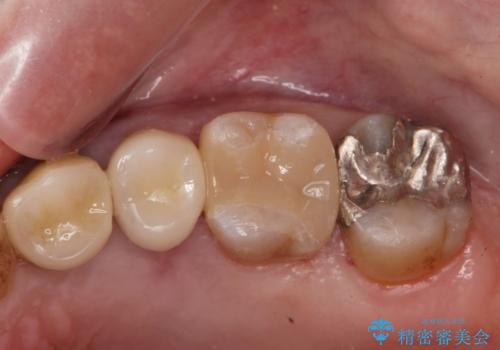

銀歯を除去し隣の歯も虫歯が見られたのでジルコニアクラウン、e-maxインレーで治療を行いました。

適合の良い被せ物、詰め物が入りました。

今後被せ物、詰め物が欠けたりしないようにナイトガードの使用をお勧めしています。